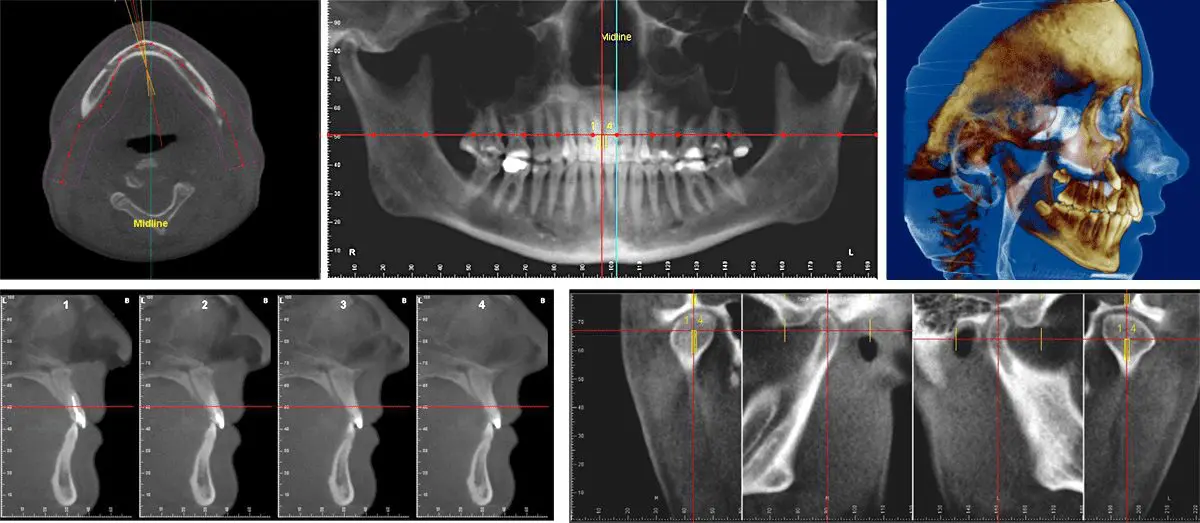

October 7th 2013, was considered as a golden day in the history of MCODS when Cone Beam Computed Tomography (CBCT) machine was inaugurated registering it as the first dental college acquiring such a machine. U. T. Khadar, Minister of Health and […]